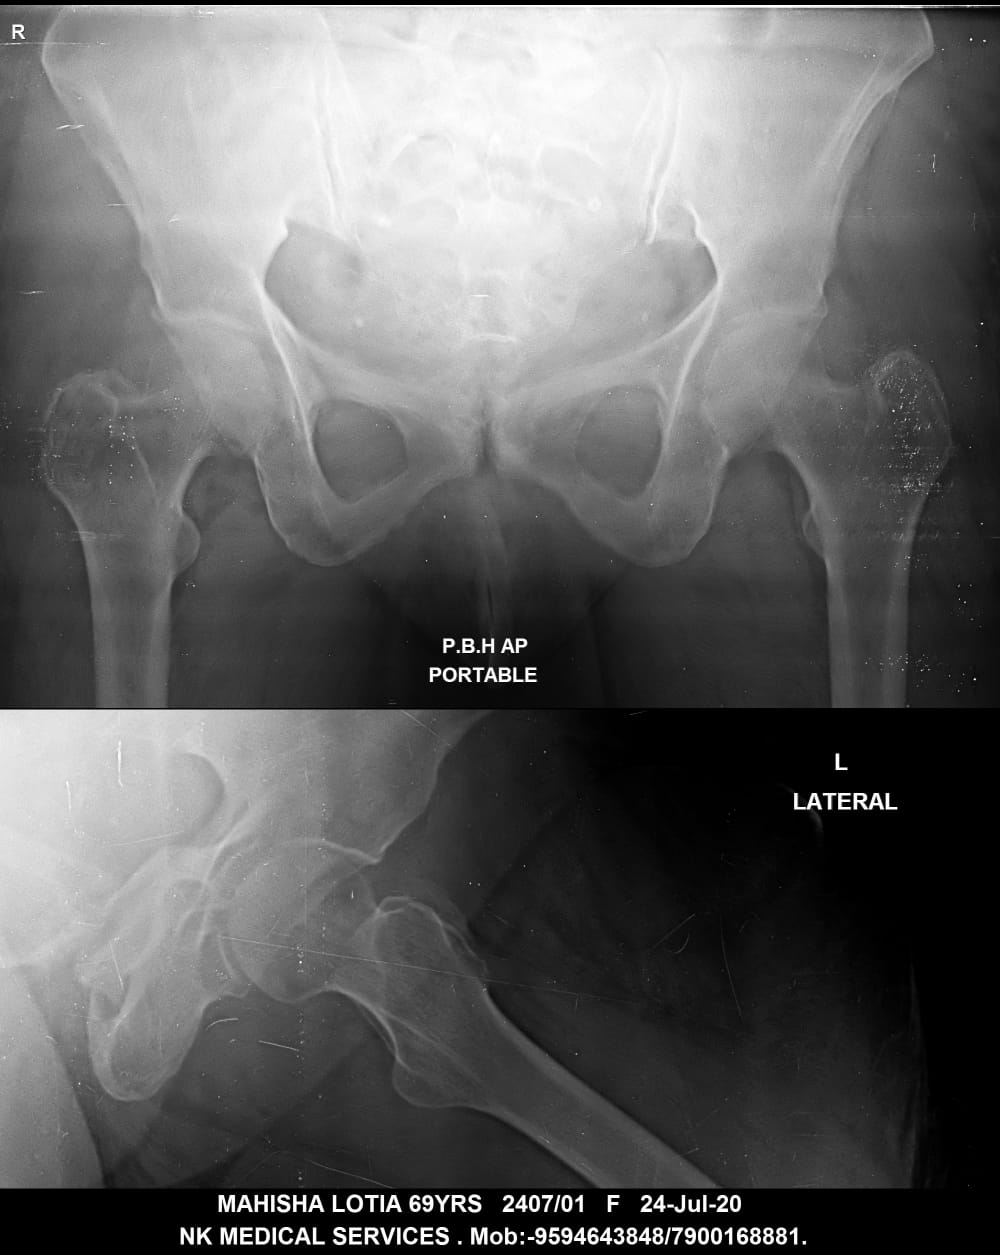

Getwell Urgent Care of Southaven uses digital X-ray technology, which uses less radiation, provides fast turnaround of images, and gives us the ability to manipulate images for more accurate readings. We follow the highest safety standards, with certified equipment and licensed radiology technologists to ensure an excellent image the first time and minimal exposure to radiation. We use digital X-ray to diagnose broken bones, certain lung conditions (e.g., pneumonia), and certain abdominal conditions.